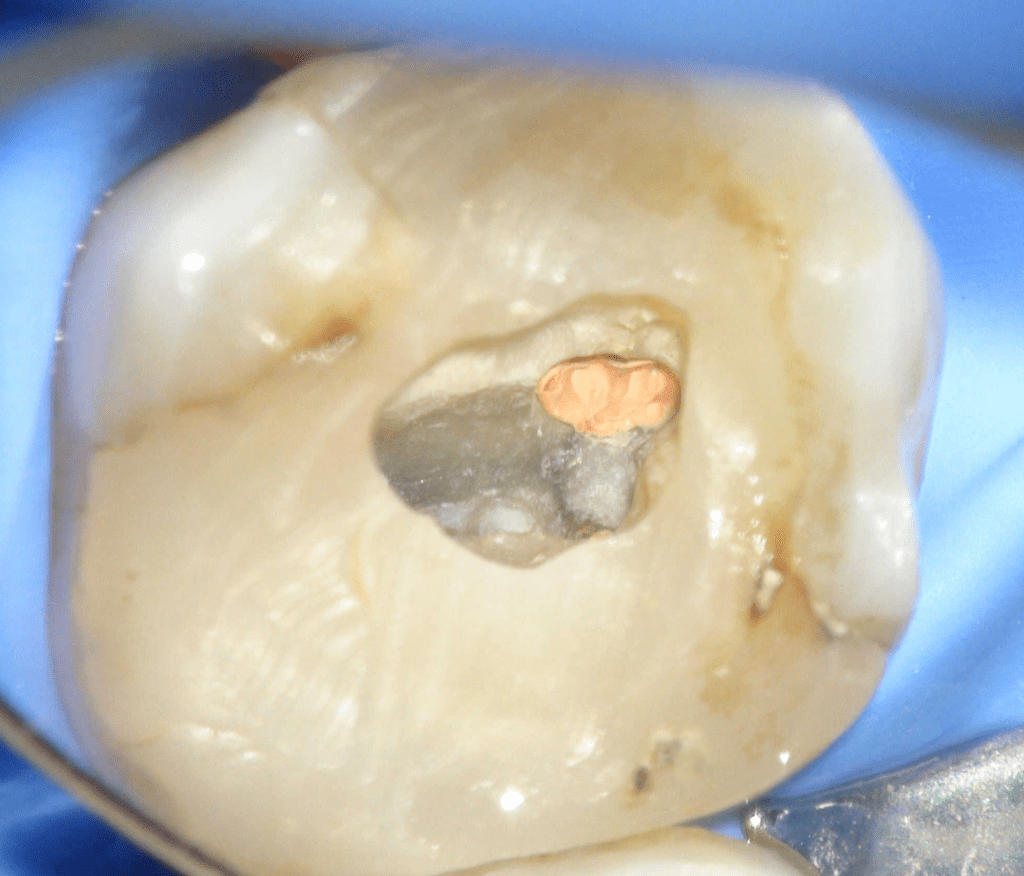

Fisura, remoción amalgama para explorar